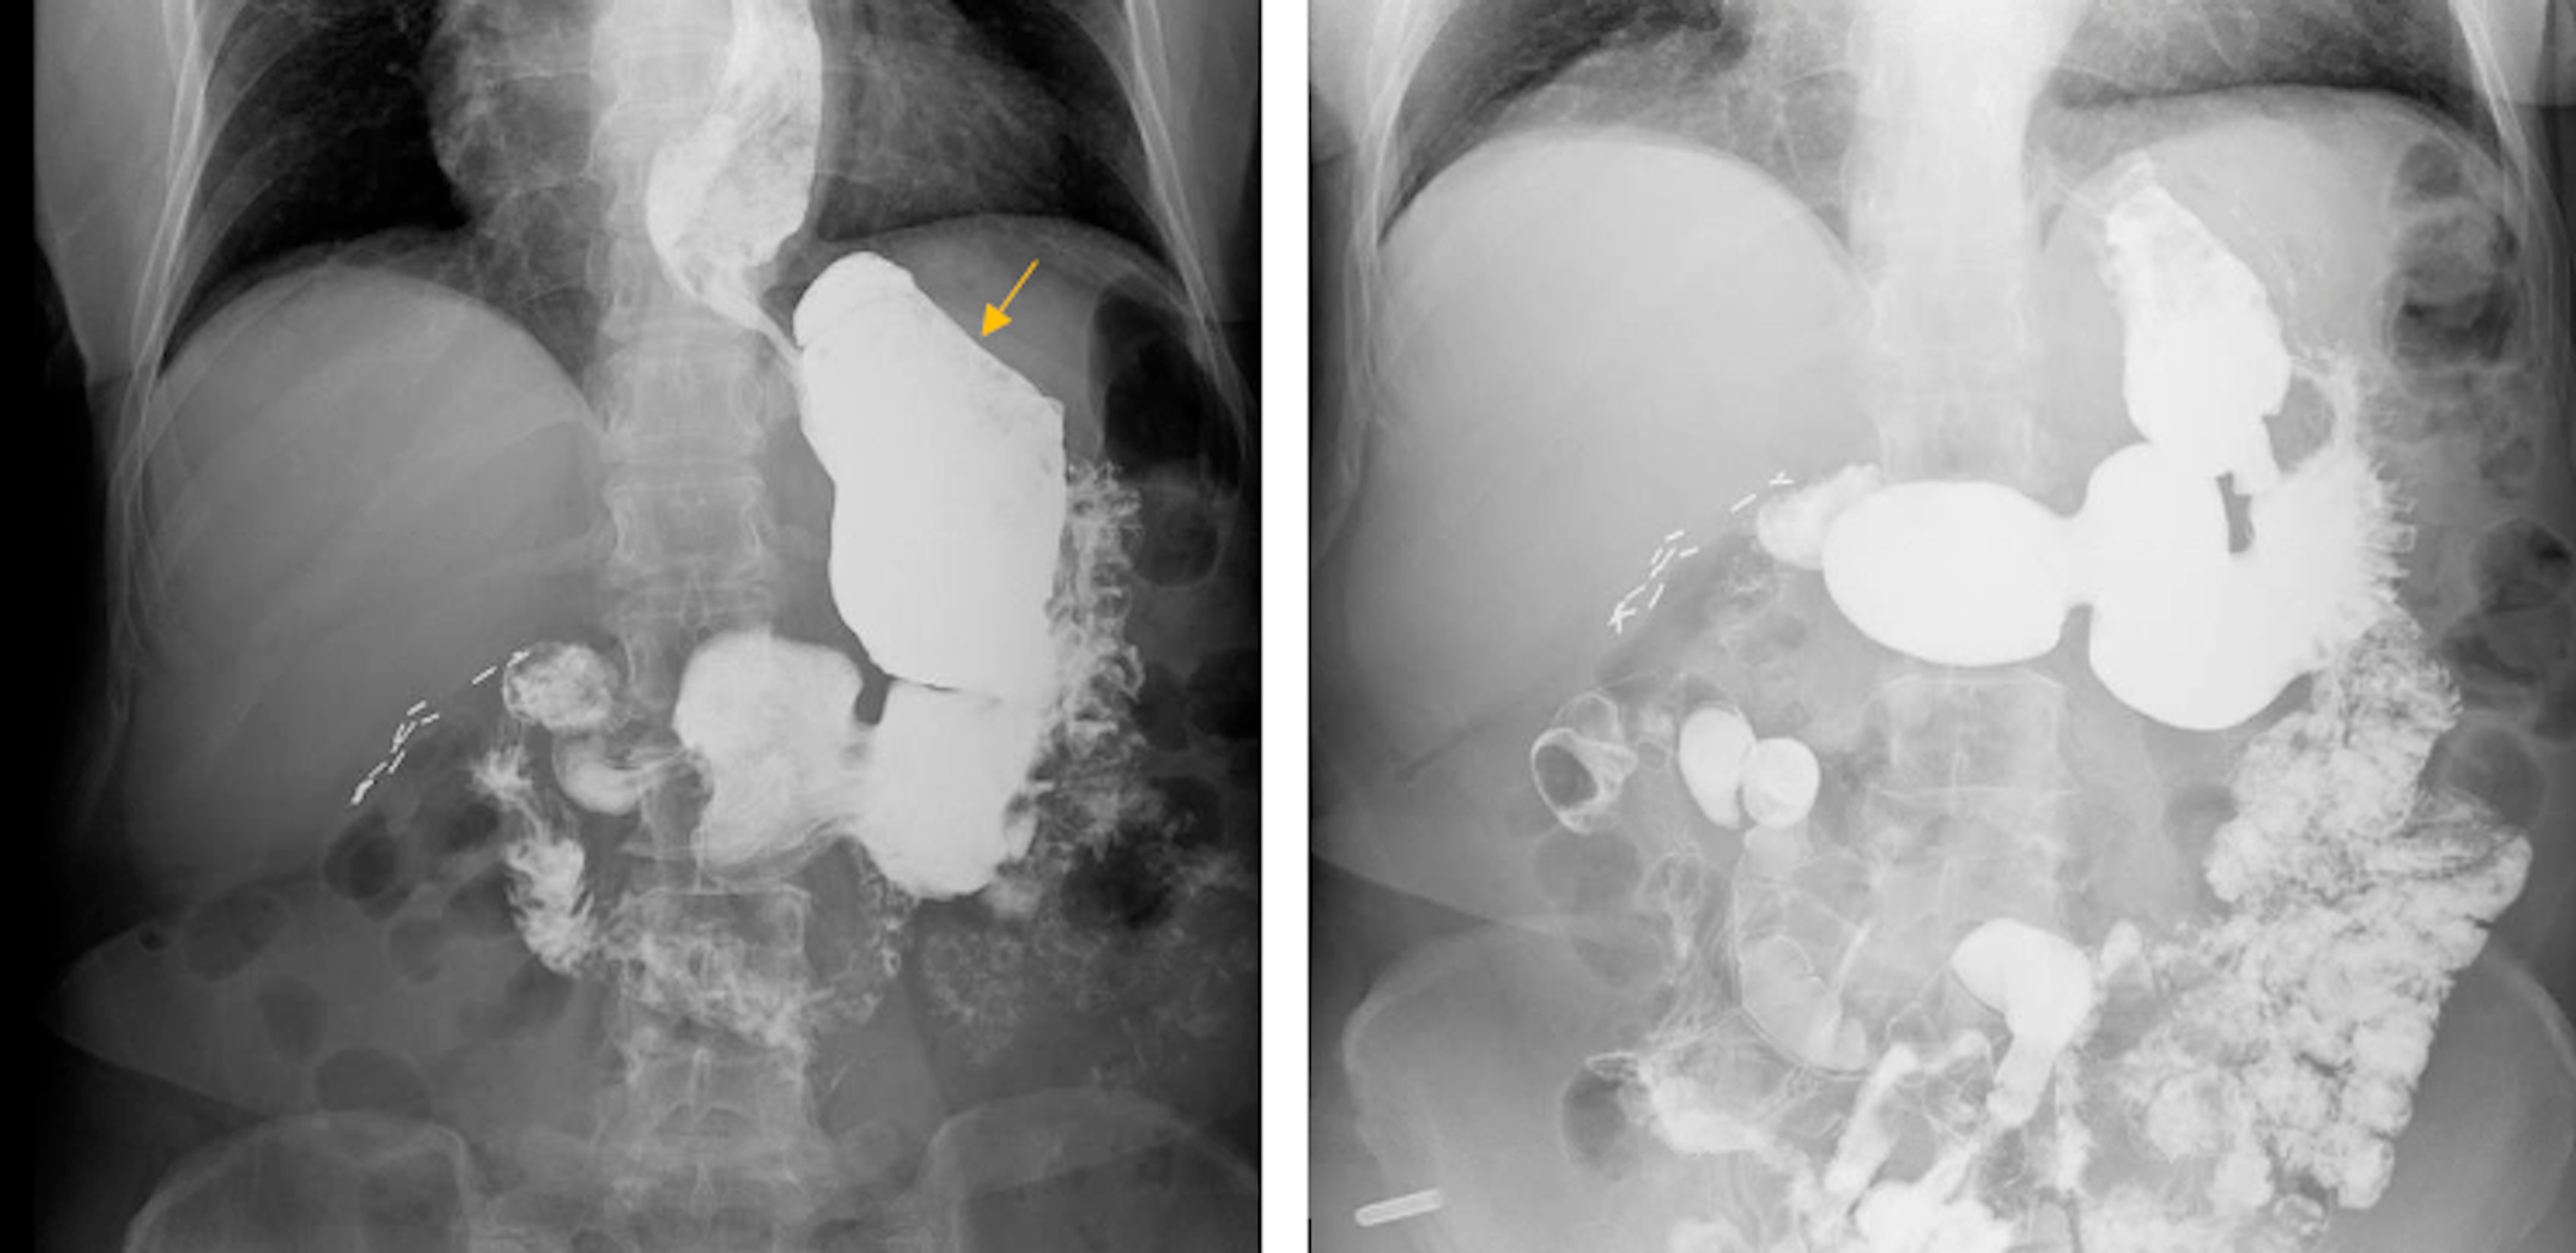

From www.researchgate.net

2012 upper GI study showing gastric bezoar (a); 2014 upper GI study Removal Of Gastric Bezoar Cpt Several factors favor their formation, 1,2 and the clinical presentation may vary, including dyspepsia, anorexia, vomiting, weight loss, abdominal pain, and sometimes intestinal. In the presence of an intestinal bezoar discovered at laparotomy. Learn about the etiology, diagnosis, and treatment. This chapter describes the surgical procedure for the removal of gastric bezoar as performed by the following approaches:. Bezoars are. Removal Of Gastric Bezoar Cpt.